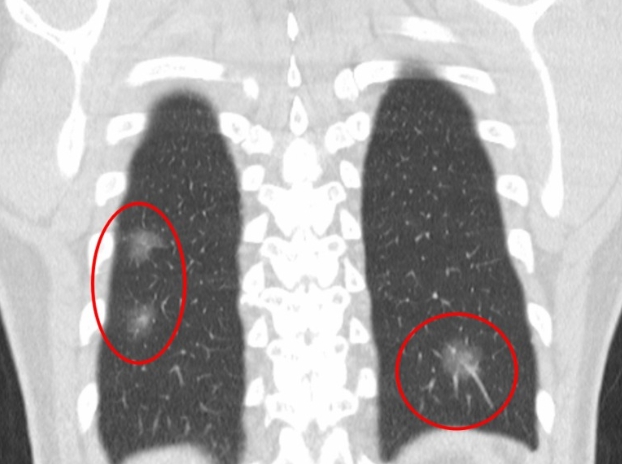

흉부CT는 병이 있는지 없는지를 넘어서, 병의 진행 정도와 주변 장기 침범 여부까지 보여줍니다. 예를 들어 폐암의 경우, 5mm 미만의 아주 작은 결절까지 찾아내고, 종양이 혈관이나 기관지에 닿았는지도 확인합니다. 초기에 잡아내면 완치율이 크게 높아지죠.

또한 폐렴이 감염인지, 결핵성인지, 종양에 의한 것인지도 구분할 수 있습니다. 엑스레이에서는 그냥 ‘흐린 그림자’로만 보이던 것도, CT에서는 염증의 경계와 내부 구조까지 뚜렷하게 드러납니다.

Q8. 흉부CT 결과에서 ‘폐결절’이 나왔다는 말은 뭔가요?

A. 흉부ct로 볼수있는 질환 폐결절은 말 그대로 폐 안에 작은 혹이 있다는 뜻입니다. 대부분 양성(암이 아님)이고, 오래된 염증이나 석회화에 의한 것일 수도 있습니다. 그러나 결절의 크기가 8mm 이상이거나, 형태가 불규칙한 경우에는 추가 검사가 필요합니다. 영상의학과에서는 결절의 밀도, 경계, 주변 변화 등을 세밀하게 분석해 암 가능성을 판단합니다.